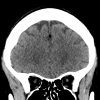

Mỡ nội sọ

Mỡ nội sọ - Ảnh 3

» Thông tin: Nam giới – 46 tuổi.

» Lâm sàng: Kiểm tra sức khỏe.